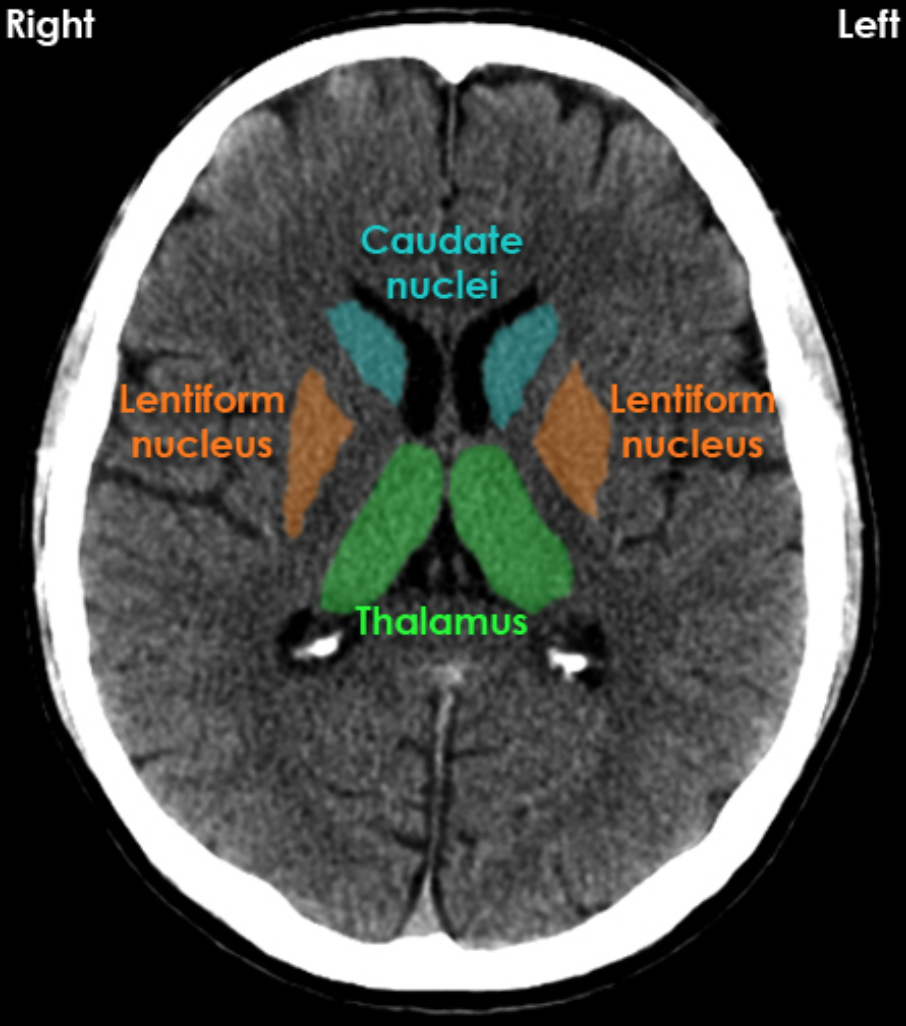

Basal Ganglia: